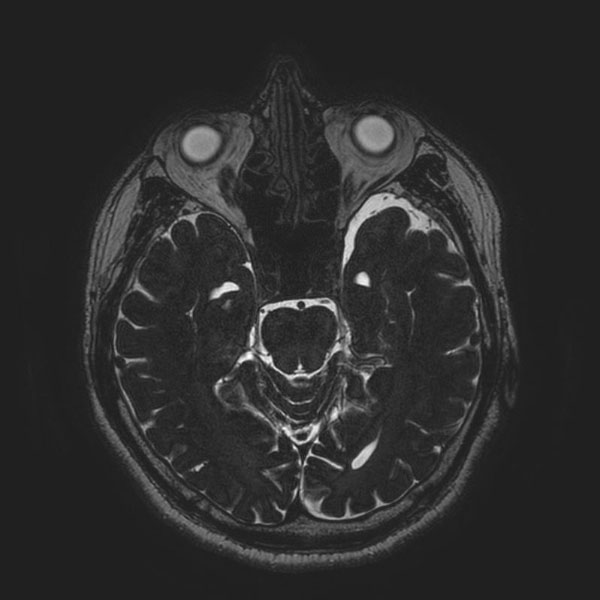

手術前

(MR1)